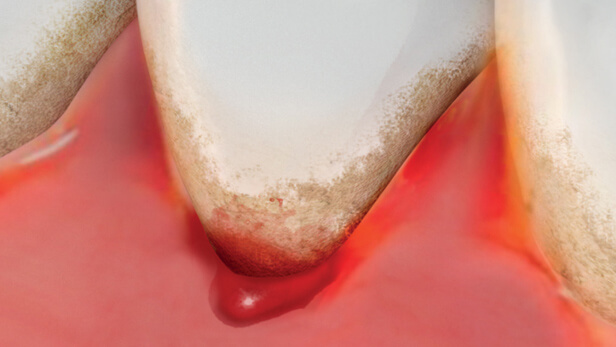

Czym jest elektrokoagulacja? Elektrokoagulacja to zabieg polegający na kontrolowanym wykorzystaniu prądu elektrycznego w celu zamknięcia naczyń krwionośnych oraz usunięcia zmienionych tkanek. W stomatologii metoda ta znajduje zastosowanie przede wszystkim w chirurgii i periodontologii. Stomatolog w nowoczesnej klinika stomatologiczna Kraków wykorzystuje…